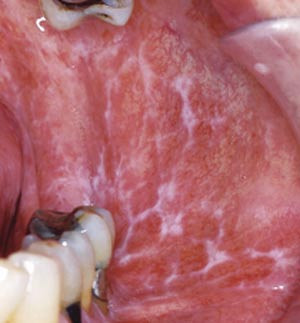

Oralt manifesterer tilstanden seg med flere ulike kliniske former, hvorav de viktigste er retikulær og erosiv lichen planus. Blandingsbilder forekommer hyppig. Den retikulære formen er vanligst og karakteriseres av et nettverk av hvite streker, oftest symmetrisk i kinnslimhinnene, tilsvarende Wickhams striae på hud (fig 4). Tungeslimhinne, gingiva og lepper kan også være affisert. Ved erosiv oral lichen planus finner man sårdanning og betydelig inflammasjon og dermed sterkere symptomer (svie, smerter, vansker med fødeinntak) enn ved den retikulære formen. Øsofageal affeksjon forekommer. Oral lichen planus er ofte behandlingsresistent, men på sikt er spontan remisjon hyppig. Verdens helseorganisasjon har karakterisert tilstanden som prekankrøs, selv om det hersker uenighet om dette blant forskere (14, 15). Genitale slimhinnelesjoner forekommer hyppig (ca. 25 %) ved både kutan og oral lichen planus.